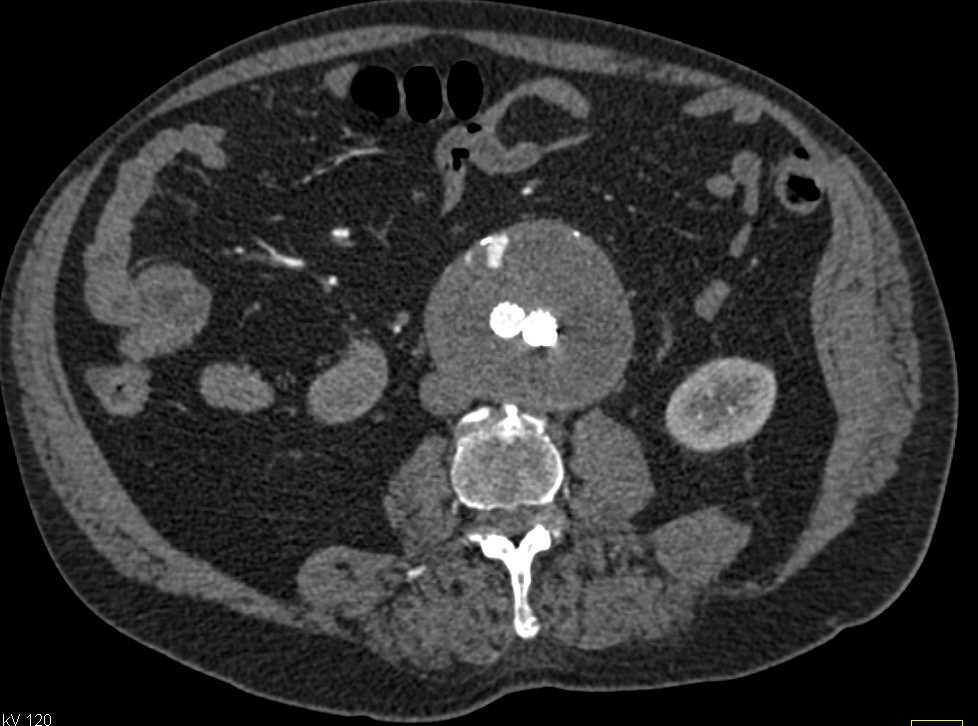

Tumor Infiltrates the Posterior Mediastinum and Encases the Aorta